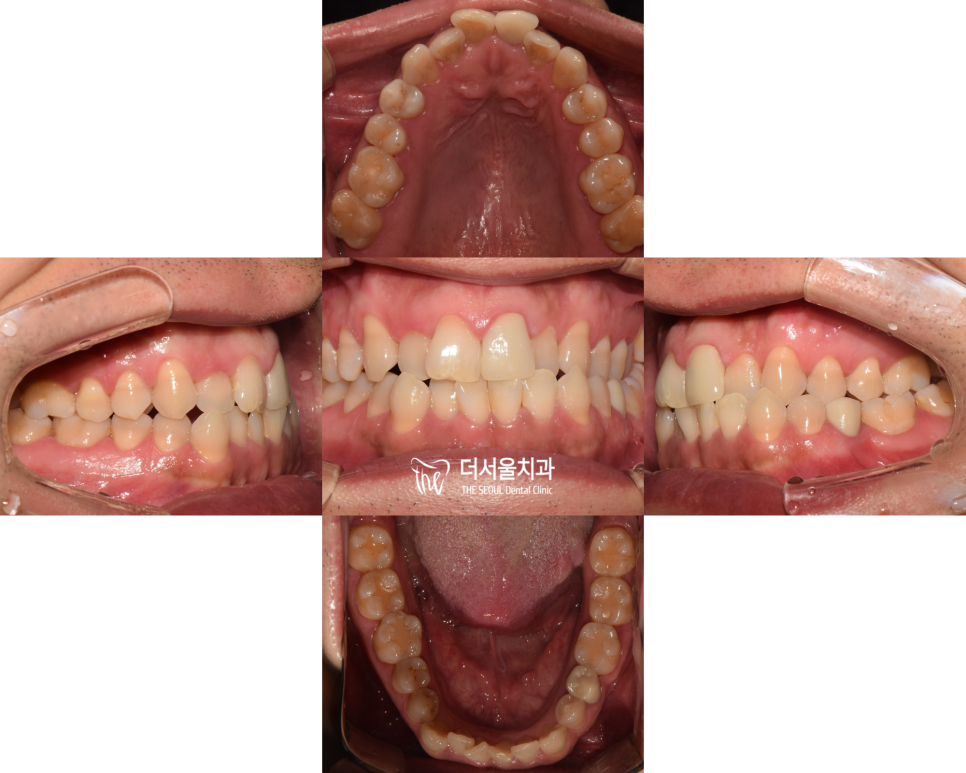

【 진단 내용 】

상악에 비해 하악 어금니가

앞으로 나와있는 Class 3급

주걱턱 케이스였습니다.

왼쪽 위,아래 어금니는

크로스 바이트(반대교합)도 관찰되었는데요.

전체적으로 봤을 때 쉽지 않은

인비절라인 케이스란 생각이 들었죠.

치열을 위에서 봤을 때

완곡한 U자 형태로 만들어야

예쁜 모습을 볼 수 있는데요.

어금니가 안쪽으로 들어가 있었기에

불규칙한 U자의 형태를 띄고 있었기에

이런 모양도 같이

인비절라인 진단 내용에 넣었습니다.